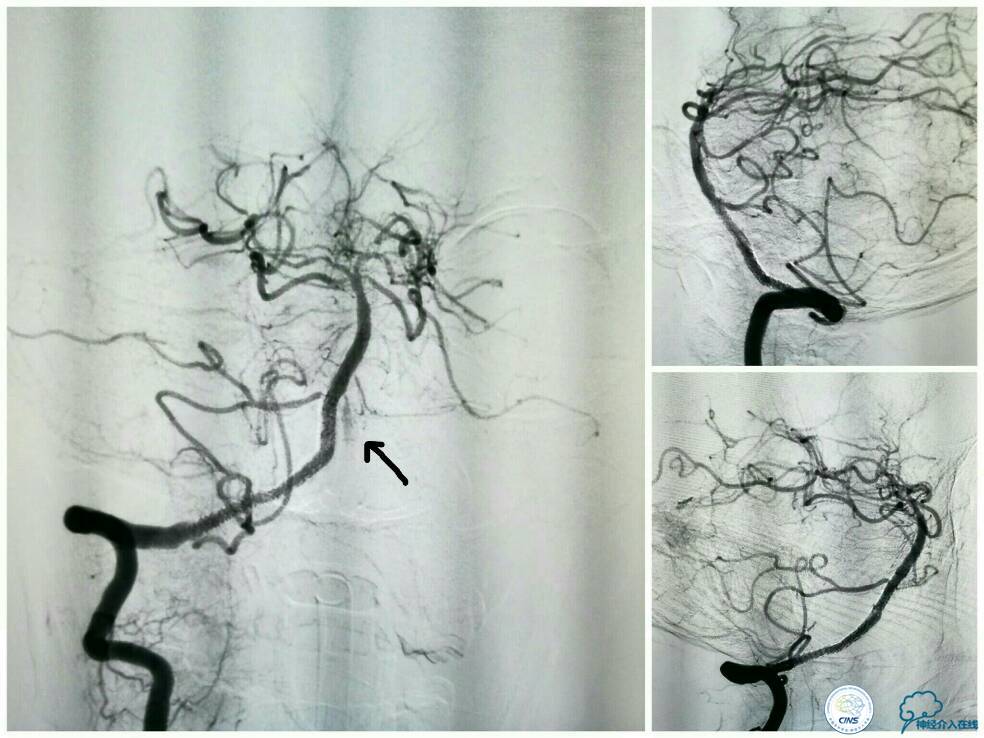

支架释放过程中给予替罗非班3 ml/h静脉持续泵入,以预防急性血栓形成。最后一枚支架释放完毕后造影显示右椎动脉V4段再通,支架贴壁良好,前向血流TICI分级3级,左椎动脉V4段逆向显影(箭头)(图11)。